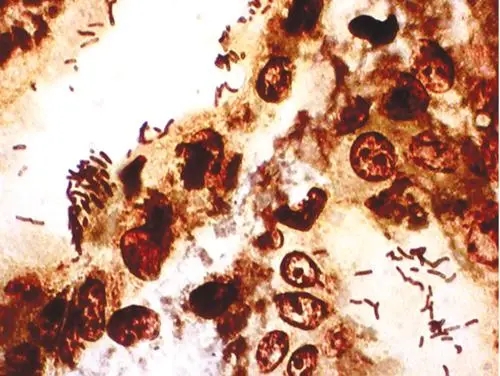

粪肠球菌革兰氏染色

粪肠球菌革兰氏染色 当前位置:首页 > 公司产品 > 产品服务 > 瑞果产品展示 > 细菌